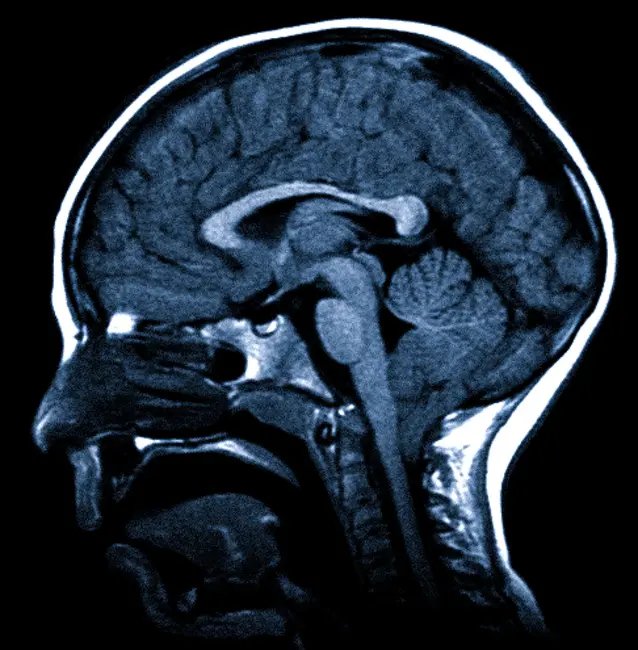

Краниовертебральный переход – это особая зона, где соединяются затылочная кость черепа и позвоночник. Этим местом часто затрагиваются дегенеративные изменения и воспаления из-за его анатомических характеристик, что влечет за собой необходимость диагностики и лечения. МРТ краниовертебрального перехода — это единственно эффективный способ осуществления быстрой и бесконтактной визуализации тканей этой области. Процедура может применяться как для первичной диагностики, так и для подтверждения наличия патологий.

Что именно можно увидеть на МРТ краниовертебрального перехода, зависит от клинической ситуации. В ходе обследования исследуются ткани этой специфической области, включая:

- Головной мозг.

- Спинной мозг.

- Кровеносные сосуды.

- Аномалия Арнольда-Киари – изменение нормального анатомического положения продолговатого мозга и мозжечка.